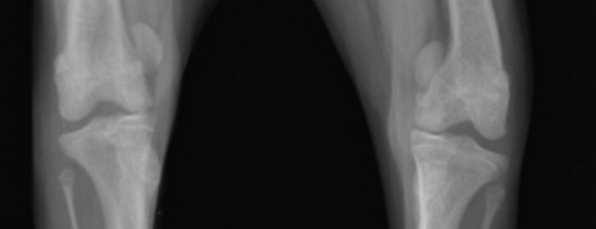

강아지 슬개골 탈구는 1단계부터 4단계까지 그 심각도를 구분하며, 단계가 높을수록 재발 가능성 또한 높아집니다. 이는 질병의 진행 정도에 따라 관절 주변 조직의 손상과 구조적 변형이 심해지기 때문입니다.

- 3단계와 4단계처럼 슬개골 탈구가 이미 심하게 진행된 경우, 무릎 관절을 둘러싼 근육, 인대, 관절낭 등의 연부 조직이 심하게 손상되고 늘어나게 됩니다.

- 또한, 슬개골이 지속적으로 이탈하면서 대퇴골의 활차구(슬개골이 움직이는 홈)가 얕아지거나 변형되고, 경골(정강이뼈)의 뒤틀림 등 뼈의 구조적인 변형까지 동반될 수 있습니다.

- 이러한 복합적인 문제들로 인해 수술 자체가 복잡해지고, 아무리 성공적으로 수술이 진행되더라도 이미 변형된 관절 구조와 늘어난 연부 조직이 다시 이완되면서 재발할 가능성이 훨씬 높아지게 됩니다.